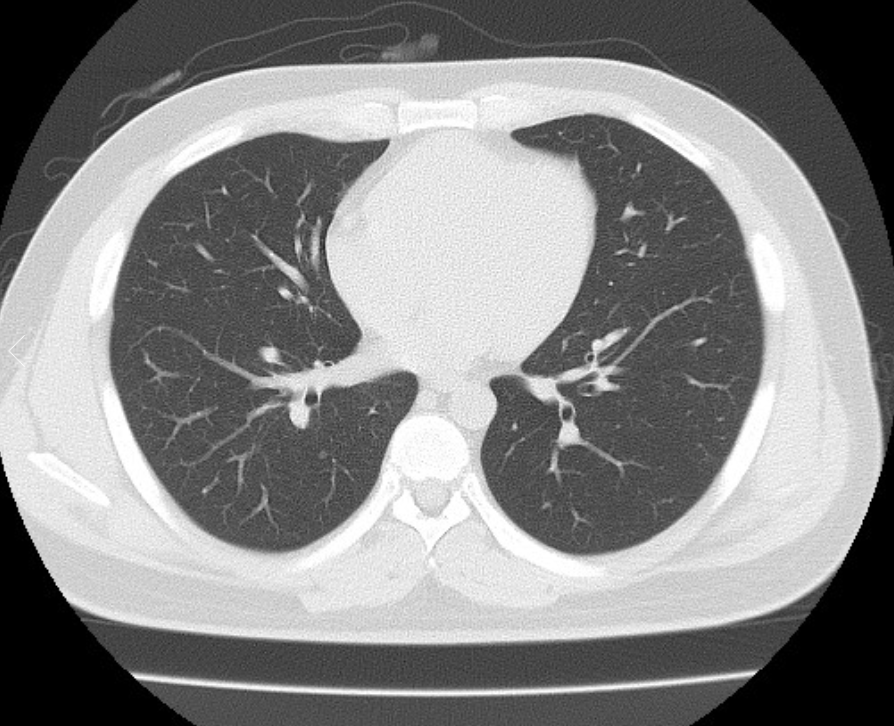

폐ct사진 받았는데 엄청 많더라구요.. 우중엽(40#)에 부분고형결절(6mm, 고형 2mm)결절이 있다고 소견을 받았는데 아래 ct사진 상 위험한 결절로 보이는지 판독좀 부탁드리겠습니다 ㅜㅜ. 다른 사진들 더 많지만 앞뒤 전후로 몇장씩만 가져왔어요..

• 1번 째 사진